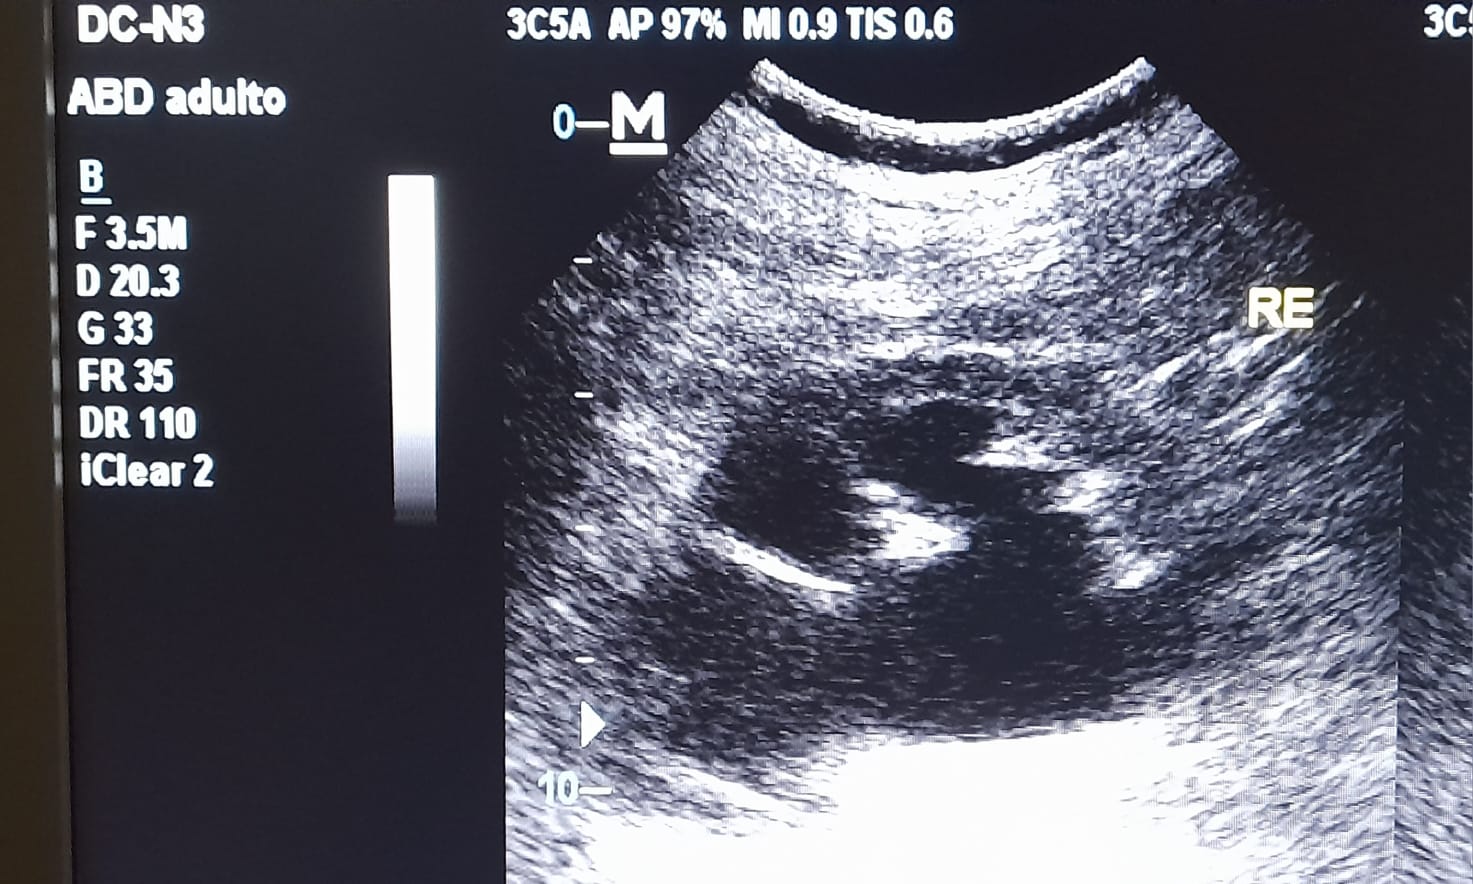

En la ecografía realizada en el ambulatorio observamos una hidronefrosis renal izquierda con líquido libre peritoneal y derivamos a urgencias de urología para estudio y manejo.